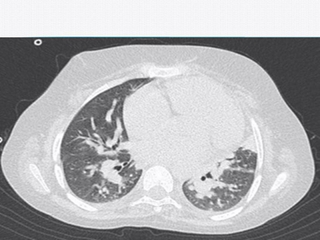

فوق تخصص رادیولوژی اطفال

دکتر رکسانا آزما